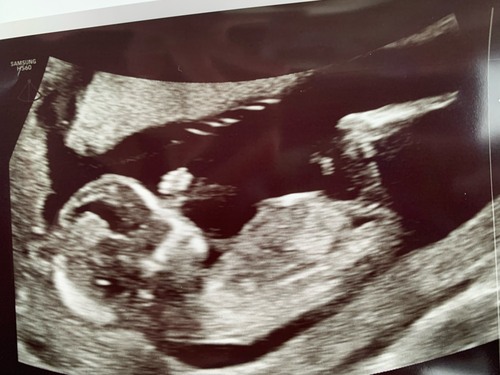

Jeetje wat een onwijs fijne uitleg, hiermee heb ik nu zelf de nub kunnen vinden uit mijn filmpje van de echo van laatst. Alleen ik twijfel heel erg wat het word?

13+6 dagen, dit was alleen het beste shot die ik kon krijgen, helaas zonder blaas en ruggengraat niet geheel mooi erop.